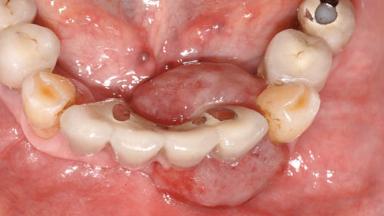

Peripheral Giant-cell Granuloma Associated with Peri-implant Tissues

Case Type Extended Space

Jaw Mandible

Area Anterior|Posterior

# of Teeth 10

# of Implants 5